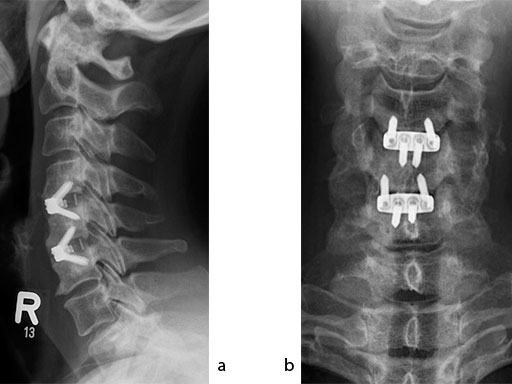

A 51-year-old woman was affected by cervical radiculo-myelopathy due to spinal and neuroforaminal stenosis. The preoperative CT scans are shown at Fig 4 and MRI at Fig 5.

The patient was treated by anterior cervical decompression and fusion (ACDF) with ZERO-P filled with ChronOS. No autologous bone graft was used. Postoperative images are shown (Fig 69).